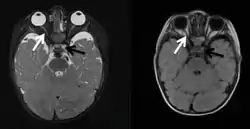

Магнітно-резонансну томографію (МРТ) використовують для візуалізації невритів, пухлин, у випадку передньої ішемічної нейропатії, у випадку внутрішньочерепної гіпертензії. При невритах у T-2 режимі можна побачити набряклий нерв із підвищеним сигналом. Чутливим є використання T-1 режиму із супресією жиру та використанням гадоліну як контрастного агента.[75] У такому випадку також відзначатимуть посилення сигналу.[75] При менінгіомі у T-1 режимі пухлина буде ізо- або гіподенсною щодо нерва, у T-2 режимі — ізо- або гіперденсною[76]. Гліома при використанні МРТ виглядає як мішкоподібне розширення нерва, гіподенсне у T-1 режимі та гіперденсне у T-2 режимі[77].

Неврити

Неврит зорового нерва — це нейропатія, у якій провідну і первинну роль відіграє запалення. Якщо запалення зачіпає диск зорового нерва, то на очному дні будуть наявні зміни диска, а для опису самого запалення можуть використовувати термін «папіліт». У 65 % запалення локалізовано поза внутрішньоочною частиною, а диск при фундоскопії виглядає нормально. У такому випадку використовують термін «ретробульбарний неврит».[89] Найчастіше неврит зорового нерва виникає у хворих на розсіяний склероз та зоровий нейромієліт[90].